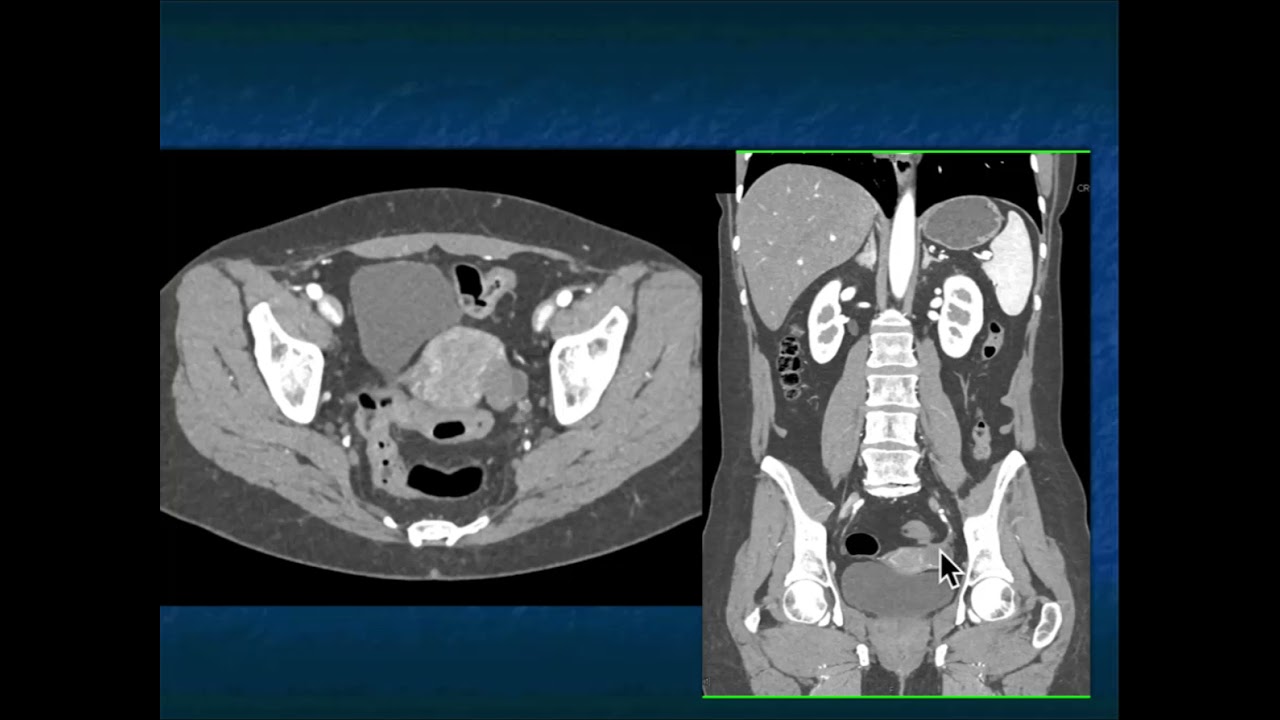

12-year-old male with history of fetal alcohol syndrome and dermal vascular abnormalities. There is a T1 isointense to skeletal muscle, T2 heterogeneous hyper- and isointense lesion with lobular margins as well as a thin peripheral rim of sclerosis in the proximal left humerus. No diffusion restriction or loss of signal on out of phase images. A single postcontrast fat-saturated image through the proximal right hand demonstrates a serpiginous enhancing soft tissue lesion at the first webspace. These imaging findings are compatible with Maffucci syndrome. Maffucci syndrome is characterized by multiple enchondromas with soft tissue hemangiomas. Male patient's are more commonly affected. Clinical symptoms are typically present birth. On physical examination hemangiomas are typically recognized as blue subcutaneous nodules. Enchondromas most commonly affected the hands and feet. The osseous and soft tissue vascular abnormalities are usually asymmetric. There is a risk of degeneration of the enchondromas to chondrosarcoma and soft tissue hemangiomas to vascular sarcomas. NMR 314 For more, visit our website at http://ctisus.com